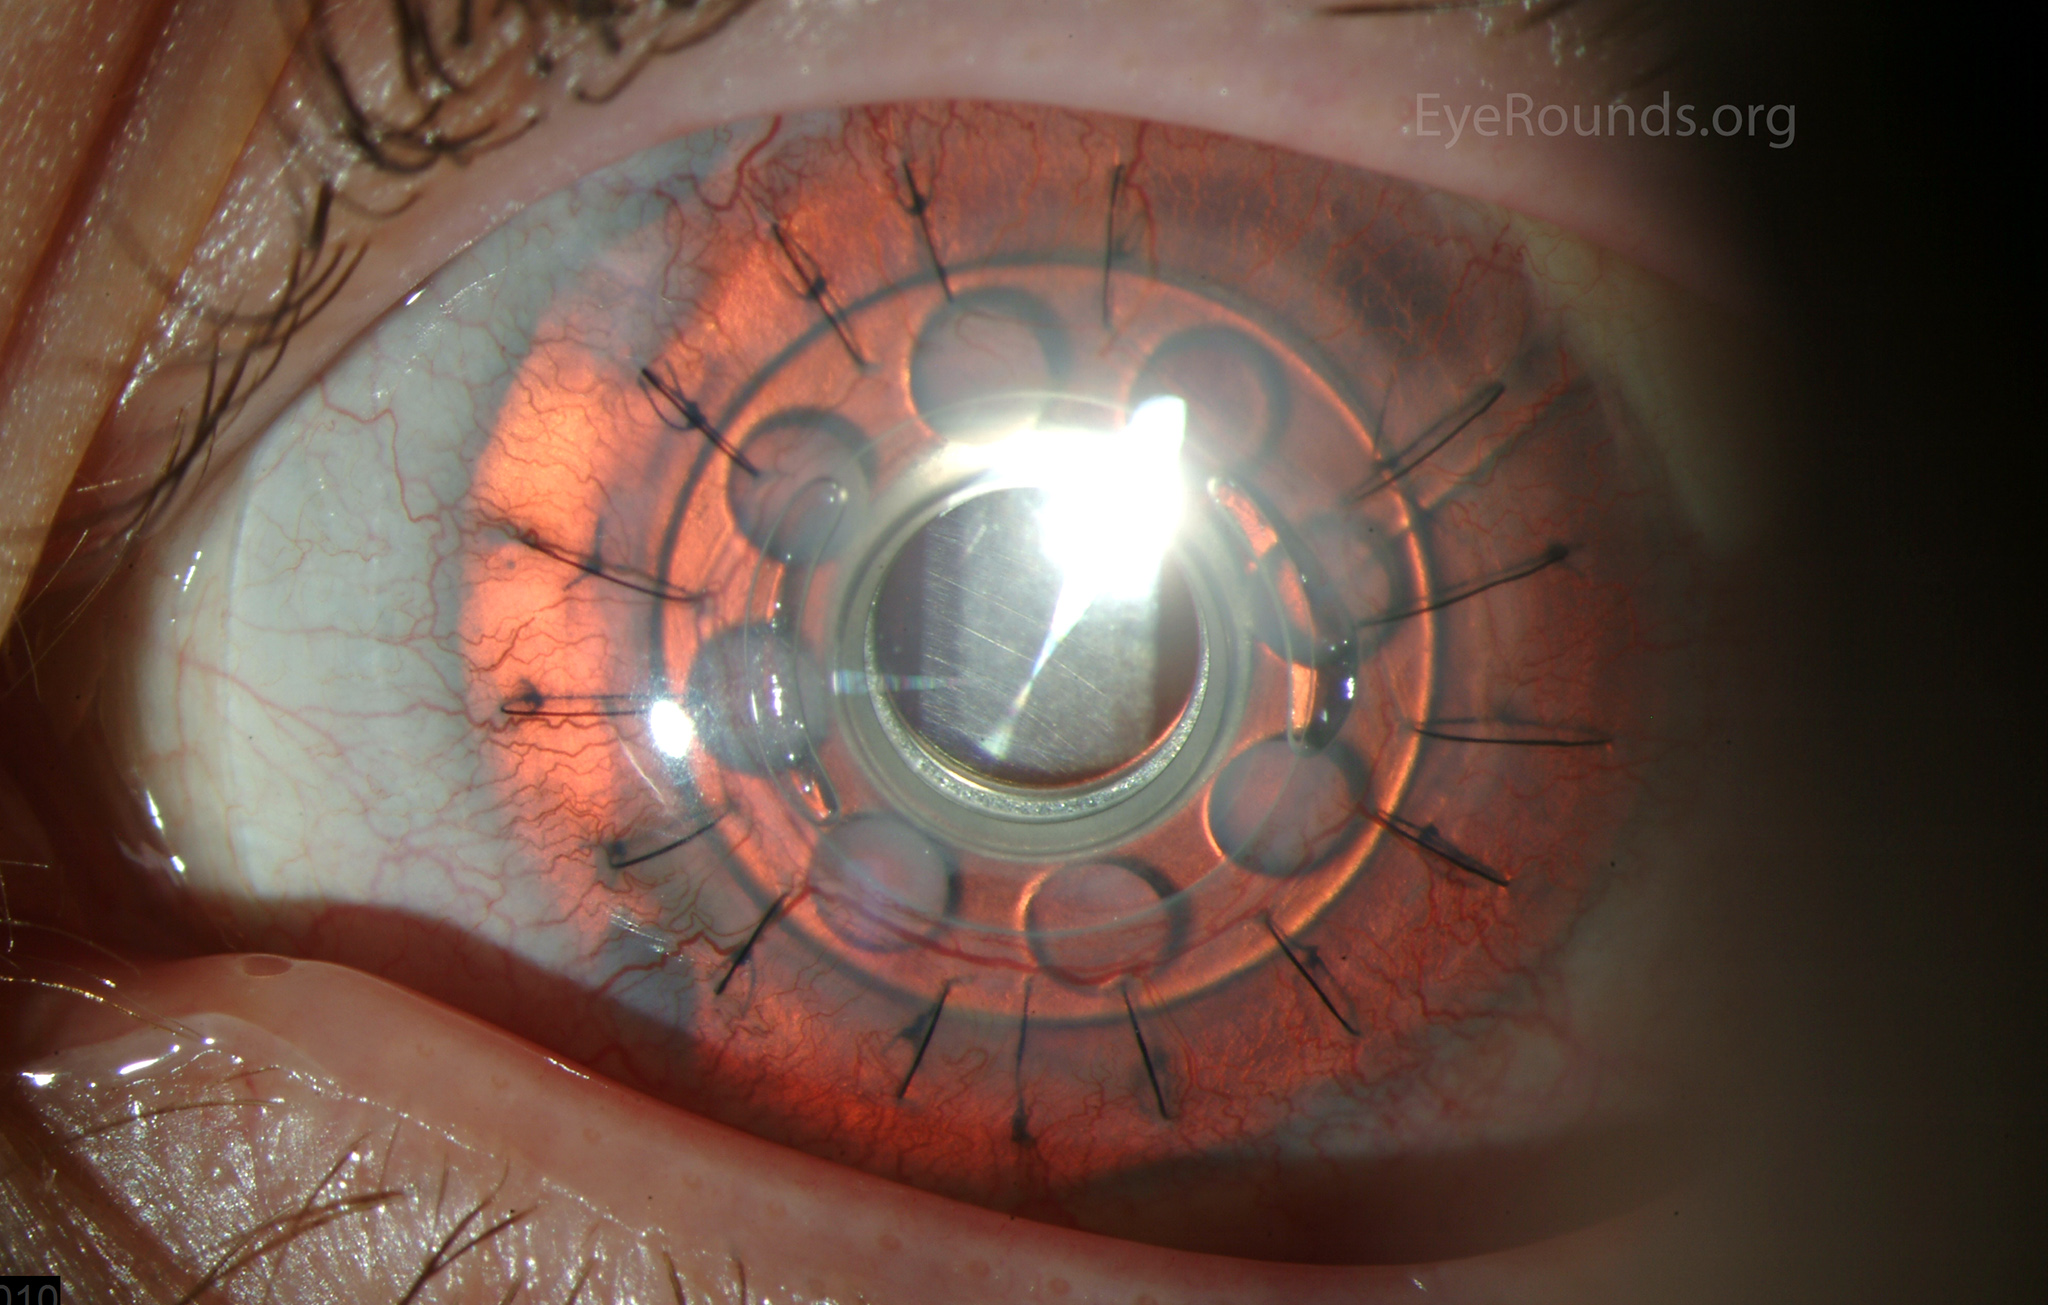

Keratoprosthesis implantation is a procedure that involves full-thickness removal of the cornea and replacement by an artificial cornea. The Boston Type I Keratoprosthesis is currently the most commonly used keratoprosthesis device in the US. It consists of a clear plastic polymethylmethacrylate (PMMA) optic and back plate sandwiched around a corneal graft and secured with a titanium locking ring (Figure 15). After the device is assembled, a partial-thickness trephination is performed on the host cornea. Full-thickness resection of the patient's cornea is then completed using curved corneal scissors. The keratoprosthesis is then secured to host tissue using interrupted or running sutures. Generally, patients who have a history of multiple failed PKs are candidates for a keratoprosthesis transplant. Other indications include severe keratitis or ocular surface disease resulting from limbal stem cell failure, such as Stevens-Johnson syndrome (Figure 16), ocular cicatricial pemphigoid, aniridia (Figure 17) and chemical injury (1, 13). The Boston Type II Keratoprosthesis is a similar device with a longer optic designed to extend through an opening made in the upper eyelid (Figure 19). It is indicated for the most severe cicatrizing ocular surface diseases.